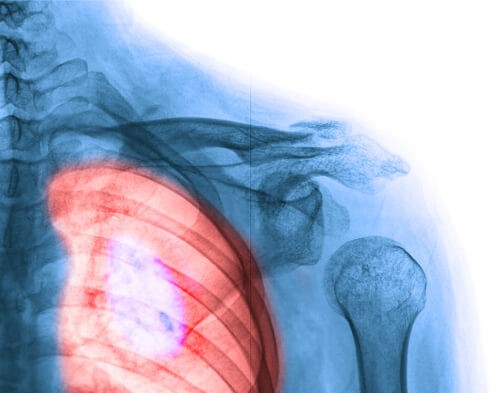

1. Brystkræft

Brystkræft har, uden tvivl, den største indvirkning på kvinder. Men vi bør nævne noget vigtigt her: den har den højeste overlevelsesrate.

Du kender sikkert nogen i din omgangskreds, der har brystkræft, eller måske har du endda mistet en du elsker på grund af denne frygtelige sygdom. Men som videnskaben gør fremskridt hver dag, overlever flere og flere kvinder. Selvundersøgelser af bryster og mammografi er nøglefaktorer til tidlig påvisning. Her er nogle få tegn og symptomer at huske på:

- En bule eller knude på brystet, brystvorten eller i armhulen, som ikke var der tidligere.

- Smerter i brystet, når man trykker.

- Ændring i brysternes størrelse.

- Uregelmæssigheder i huden: Farveændring, mavesår, appelsinskal-lignende konsistens.

- Mindre mobilitet på den ene side, når du hæver armene.

- Indsunkne brystvorter.